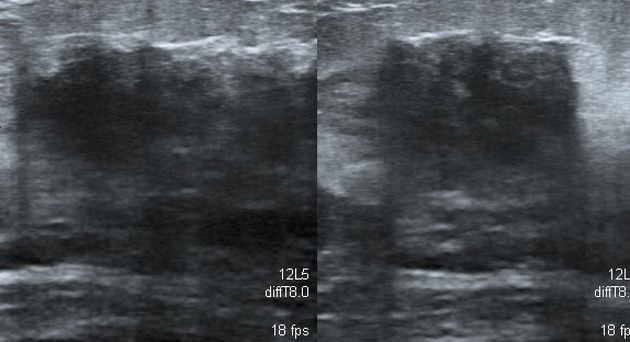

• The mammographic and sonographic features of diabetic mastopathy may be suspicious for malignancy:

• Ultrasound may show an irregular hypoechoic mass with posterior shadowing.

diabetic-fibrous-mastopathy-blueunknown